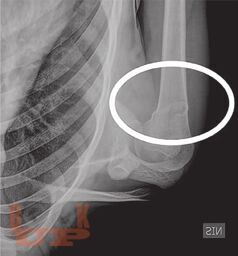

В книге рассмотрены вопросы применения методов визуализации при проведении судебно-медицинской экспертизы живых лиц и трупов. Особое внимание уделено судебно-медицинскому значению рентгенографии, посмертной компьютерной томографии и посмертной магнитно-резонансной томографии. Описаны возможности посмертной ангиографии для визуализации повреждений кровеносных сосудов. Авторы критически характеризуют преимущества и недостатки так называемой виртуальной аутопсии.